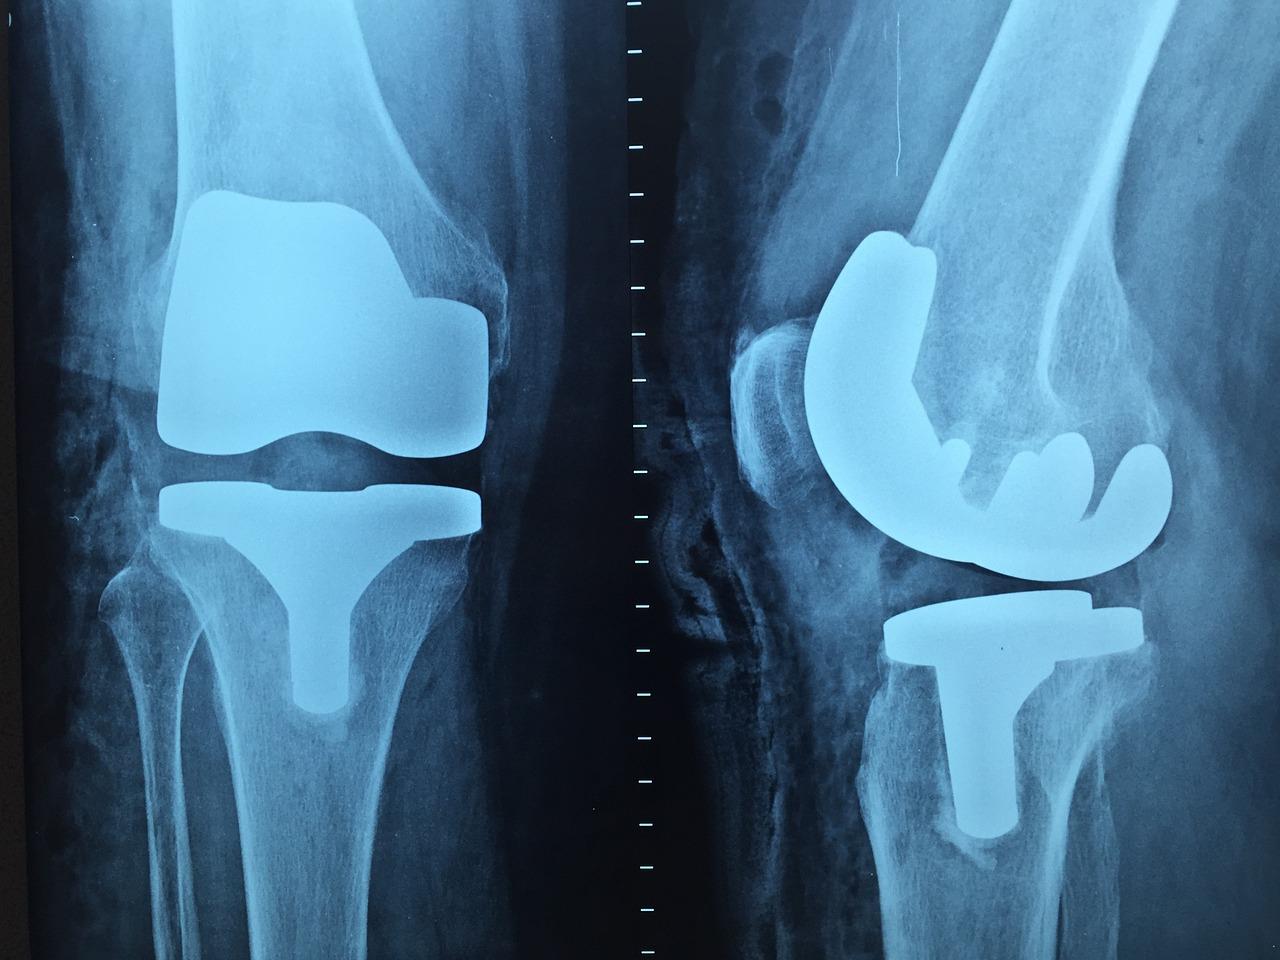

Heb je ooit last gehad van pijnlijke gewrichten of spieren die je dagelijkse activiteiten belemmeren? Of heb je sportblessures opgelopen die je prestaties beïnvloeden? Dan kan Orthopedie in Etten-Leur de oplossing bieden. Deze blogpost onderzoekt hoe orthopedische zorg in Etten-Leur lokale bewoners, sportliefhebbers en senioren ondersteunt bij het verbeteren van hun mobiliteit en levenskwaliteit. De Belang van Orthopedische Zorg voor Lokale BewonersOrthopedische zorg speelt een cruciale rol in het dagelijks leven van de inwoners van Etten-Leur. Het kan helpen bij het verlichten van chronische pijn, het herstellen van mobiliteit na een blessure en bij het verbeteren van de algehele kwaliteit van leven. Dagelijkse Voordelen van Orthopedische ZorgVoor veel mensen is het moeilijk om dagelijkse activiteiten uit te voeren als ze last hebben van aandoeningen aan het bewegingsapparaat. Orthopedische zorg biedt behandelingen die helpen bij het verlichten van pijn en het herstellen van de functie, waardoor patiënten hun normale activiteiten kunnen hervatten. Specifieke Uitdagingen in de GemeenschapLokale bewoners van Etten-Leur kunnen te maken hebben met verschillende uitdagingen, zoals werkgerelateerde blessures of chronische aandoeningen zoals artritis. Orthopedische artsen in de regio kunnen gespecialiseerde behandelingen bieden om deze problemen aan te pakken en de levenskwaliteit van patiënten te verbeteren. Hoe Orthopedie Lokale Problemen AanpaktOrthopedische specialisten in Etten-Leur bieden een breed scala aan diensten, van diagnostische beeldvorming tot chirurgische ingrepen en revalidatie. Deze uitgebreide aanpak zorgt ervoor dat patiënten de best mogelijke zorg krijgen voor hun specifieke behoeften. Orthopedische Zorg voor SportliefhebbersSportliefhebbers lopen vaak het risico op blessures door hun intensieve activiteiten. Orthopedische zorg kan helpen bij het snel en effectief behandelen van deze blessures, zodat sporters weer optimaal kunnen presteren. Veelvoorkomende SportblessuresEnkele veelvoorkomende sportblessures zijn verstuikingen, verrekkingen en peesontstekingen. Deze kunnen pijnlijk zijn en de prestaties van een sporter aanzienlijk beïnvloeden. Gespecialiseerde Zorg voor AtletenOrthopedische klinieken in Etten-Leur bieden gespecialiseerde zorg voor atleten, met behandelingen die gericht zijn op snel herstel en preventie van toekomstige blessures. Dit omvat fysiotherapie, injecties en, indien nodig, chirurgische ingrepen. Succesverhalen van Lokale SportliefhebbersVeel lokale sporters hebben baat gehad bij de zorg van orthopedische specialisten in Etten-Leur. Bijvoorbeeld, een lokale voetballer herstelde snel van een knieblessure dankzij een combinatie van fysiotherapie en een minimaal invasieve chirurgische ingreep. Ondersteuning van Senioren met Orthopedische DienstenSenioren hebben vaak unieke orthopedische behoeften, zoals behandelingen voor artritis en osteoporose. Orthopedische zorg in Etten-Leur biedt op maat gemaakte behandelingen die rekening houden met de specifieke behoeften van oudere patiënten. Unieke Behoeften van OuderenNaarmate we ouder worden, worden onze botten en gewrichten kwetsbaarder. Senioren kunnen te maken krijgen met aandoeningen zoals artrose, die pijn en mobiliteitsproblemen veroorzaken. Beschikbare Behandelingen voor SeniorenEtten-Leur biedt diverse behandelingen voor senioren, inclusief medicatie, fysiotherapie en chirurgische ingrepen zoals gewrichtsvervangingen. Deze behandelingen zijn ontworpen om pijn te verlichten en de mobiliteit te verbeteren. Voorbeelden van Ouderen die Baat Hebben bij OrthopedieVeel senioren in Etten-Leur hebben hun mobiliteit en levenskwaliteit verbeterd dankzij orthopedische zorg. Een voorbeeld is een oudere vrouw die dankzij een heupprothese weer zelfstandig kon wandelen en haar dagelijkse activiteiten hervatte. De Rol van Technologie in Orthopedische ZorgTechnologische vooruitgang heeft de orthopedische zorg aanzienlijk verbeterd. Moderne technologieën maken nauwkeurigere diagnoses en effectievere behandelingen mogelijk. Innovaties in Orthopedische TechnologieGeavanceerde beeldvormingstechnieken zoals MRI en CT-scans stellen artsen in staat om gedetailleerde beelden van het bewegingsapparaat te verkrijgen, wat helpt bij het stellen van nauwkeurige diagnoses en het plannen van behandelingen. Voordelen van Geavanceerde BehandelmethodenModerne behandelingen, zoals minimaal invasieve chirurgie en robotchirurgie, bieden tal van voordelen, waaronder kortere hersteltijden en minder postoperatieve complicaties. Vooruitgang in Orthopedische Behandelingen in Etten-LeurOrthopedische centra in Etten-Leur maken gebruik van de nieuwste technologieën om patiënten de best mogelijke zorg te bieden. Dit omvat het gebruik van geavanceerde protheses en innovatieve revalidatieprogramma’s. Gemeenschapsbetrokkenheid en GezondheidsbewustzijnOrthopedische klinieken in Etten-Leur organiseren regelmatig evenementen en initiatieven om de gemeenschap te betrekken en bewustzijn te creëren over het belang van orthopedische gezondheid. Initiatieven en EvenementenLokale klinieken organiseren workshops en seminars over het voorkomen en behandelen van orthopedische aandoeningen. Deze evenementen bieden waardevolle informatie en praktische tips voor het onderhouden van een gezonde levensstijl. Tips voor het Behouden van Orthopedische GezondheidEnkele eenvoudige tips voor het behoud van een goede orthopedische gezondheid zijn het regelmatig doen van oefeningen om de spieren en gewrichten te versterken, het handhaven van een gezond gewicht en het vermijden van risicovolle activiteiten die letsel kunnen veroorzaken. Preventie van Blessures en AandoeningenPreventieve maatregelen, zoals het dragen van geschikt schoeisel en het gebruik van beschermende uitrusting tijdens het sporten, kunnen helpen bij het voorkomen van blessures. Het is ook belangrijk om regelmatig medische controles te ondergaan om mogelijke problemen vroegtijdig op te sporen. ConclusieOrthopedie in Etten-Leur biedt tal van voordelen voor lokale bewoners, sportliefhebbers en senioren. Door gebruik te maken van geavanceerde technologieën en op maat gemaakte behandelingen helpt de orthopedische gemeenschap patiënten hun mobiliteit te herstellen en hun levenskwaliteit te verbeteren. Het is van cruciaal belang dat inwoners van Etten-Leur prioriteit geven aan hun orthopedische gezondheid en actief betrokken blijven bij hun zorgproces. Voor meer informatie en om te ontdekken hoe orthopedische zorg jou kan helpen, neem contact op ettenleurnu.nl met een lokale specialist en begin vandaag nog met het verbeteren van je mobiliteit en welzijn. |